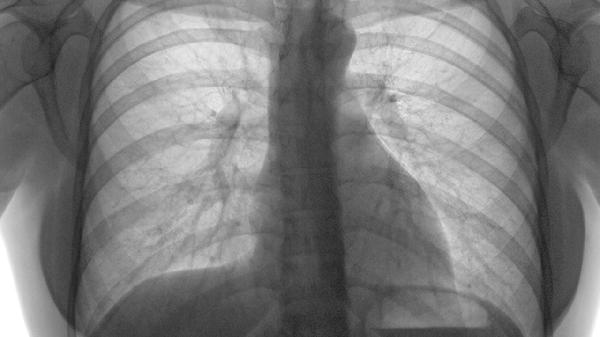

肋骨骨折恢复期间应注意保持均衡饮食,适当增加富含钙质和维生素D的食物摄入,如牛奶、豆制品、深海鱼类等,有助于骨骼愈合。避免吸烟和饮酒,这些习惯可能影响骨折愈合速度。可进行适度的上肢功能锻炼,但需避免负重活动。定期复查X线片评估骨折愈合情况,如有异常症状及时就医。保持良好作息习惯,避免过度劳累,逐步恢复日常活动。